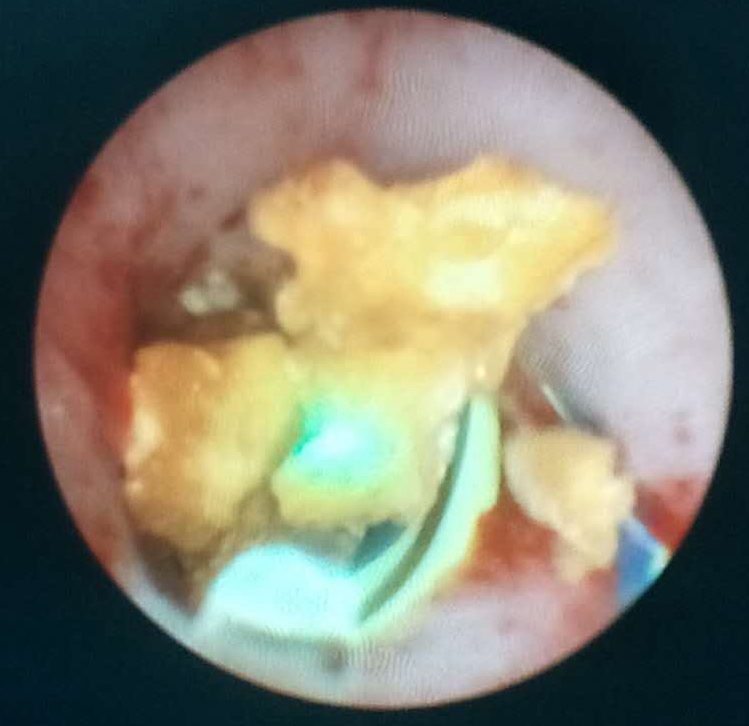

近日,我院泌尿外科成功开展复杂性上尿路结石输尿管硬镜联合输尿管软镜碎石术,术程顺利,目前患者已康复出院。

患者,老年男性,双侧输尿管结石,右肾结石,双肾积水,曾因泌尿系结石先后就诊于省级医院行手术治疗,此次因双肾积水,肾功能不全经多方打听来我院泌尿外科就诊。科室主任李朝明及其团队认真研究患者病情,综合考虑患者年龄、病史、手术史等,积极完善术前检查后,最终决定选择输尿管硬镜联合输尿管软镜为患者同时行双侧输尿管结石及右肾结石手术治疗。手术过程顺利,术后患者恢复良好,疗效显著。

我院泌尿外科一直关注本专业最前沿、最有效、最安全最高的微创技术,该手术的顺利开展,标志着我院泌尿外科在输尿管硬镜联合软镜治疗方面实现了新的突破,在治疗复杂性上尿路疾病方面又跨上了新的台阶,必将对上尿路结石的诊治产生深远的影响。